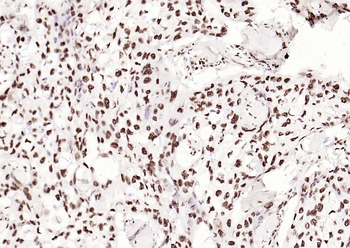

Phospho-Smad3 (Ser423 + Ser425) Rabbit Polyclonal Antibody [orb6983]

FC, IF, IHC-Fr, IHC-P, WB

Bovine, Canine, Equine, Gallus

Human, Mouse, Porcine, Rat

Rabbit

Polyclonal

Unconjugated

100 μl, 200 μl, 50 μlPhospho-SMAD5 (Ser463 + Ser465) Recombinant Rabbit Monoclonal Antibody [orb559123]